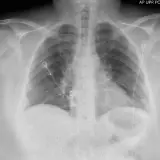

Chest Radiographs

Review cases with classic "textbook" pathology. Once you've mastered the basics, move on to practice cases with more challenging or subtle findings.

Oftentimes the key to nailing a difficult radiology case is having seen a similar case before. Practice with over 1,500 carefully selected cases covering a comprehensive list of diagnoses.

Master classic and atypical appearances of pathologies more efficiently than haphazardly reviewing cases at work. Cases include sample reports, focused discussions, annotated images, and reputable references.